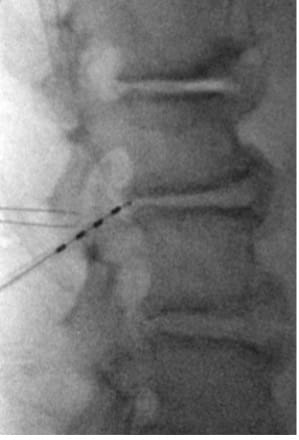

- In PA view, introduce guide needle just off midline from the superior L4 SP border towards the ipsilateral L3 TP–SAP junction marker; in lateral view, advance anteriorly to TP to traverse L2–L3 intertransversarii (~45°).

- In the lateral view, advance the guidewire towards the inferior dorsal L2 body; adjust depth if resistance is encountered. Prior to removing the guide needle and exchanging for the introducer sheath/dilator, use a #11 scalpel to make a stab incision along the guide needle trajectory adjacent to the L4 SP to create room for the introducer sheath/dilator.

- Insert lead anterior to TP; retract introducer sheath to deploy lead and confirm tine engagement around intertransversarii via push–pull test under low-dose live fluoroscopy in lateral and AP view.